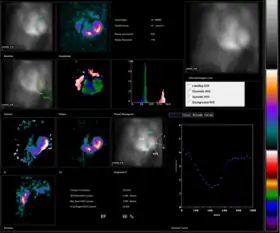

Normail MUGA scan | |

Radionuclide angiography is an area of nuclear medicine which specialises in imaging to show the functionality of the right and left ventricles of the heart, thus allowing informed diagnostic intervention in heart failure. It involves use of a radiopharmaceutical, injected into a patient, and a gamma camera for acquisition. A MUGA scan (multigated acquisition) involves an acquisition triggered (gated) at different points of the cardiac cycle. MUGA scanning is also called equilibrium radionuclide angiocardiography, radionuclide ventriculography (RNVG), or gated blood pool imaging, as well as SYMA scanning (synchronized multigated acquisition scanning).

The patient is placed under a gamma camera, which detects the low-level 140 keV gamma radiation being given off by Technetium-99m (99mTc). As the gamma camera images are acquired, the patient's heart beat is used to 'gate' the acquisition. The final result is a series of images of the heart (usually sixteen), one at each stage of the cardiac cycle.

The resulting images show that the volumetrically derived blood pools in the chambers of the heart and timed images may be computationally interpreted to calculate the ejection fraction and injection fraction of the heart. The Massardo method can be used to calculate ventricle volumes. This nuclear medicine scan yields an accurate, inexpensive and easily reproducible means of measuring and monitoring the ejection and injection fractions of the ventricles, which are one of many of the important clinical metrics in assessing global heart performance.